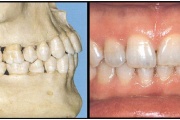

Valehambumus

Hammaste asendianomaaliad on tingitud tavaliselt arenguhäirest.

Sümptomid:

probleemid kõnega

probleemid neelamisega

suuhingamine